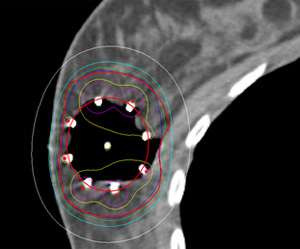

Examples show how the radiation dose (the colored lines, with the white lines representing 50% of the dose) is targeted to the area where the original tumor was using three different partial breast radiation techniques (SAVI, Contura, Tube and Button).

This is in contrast to these examples of standard whole breast radiation where the entire breast is considered the target.